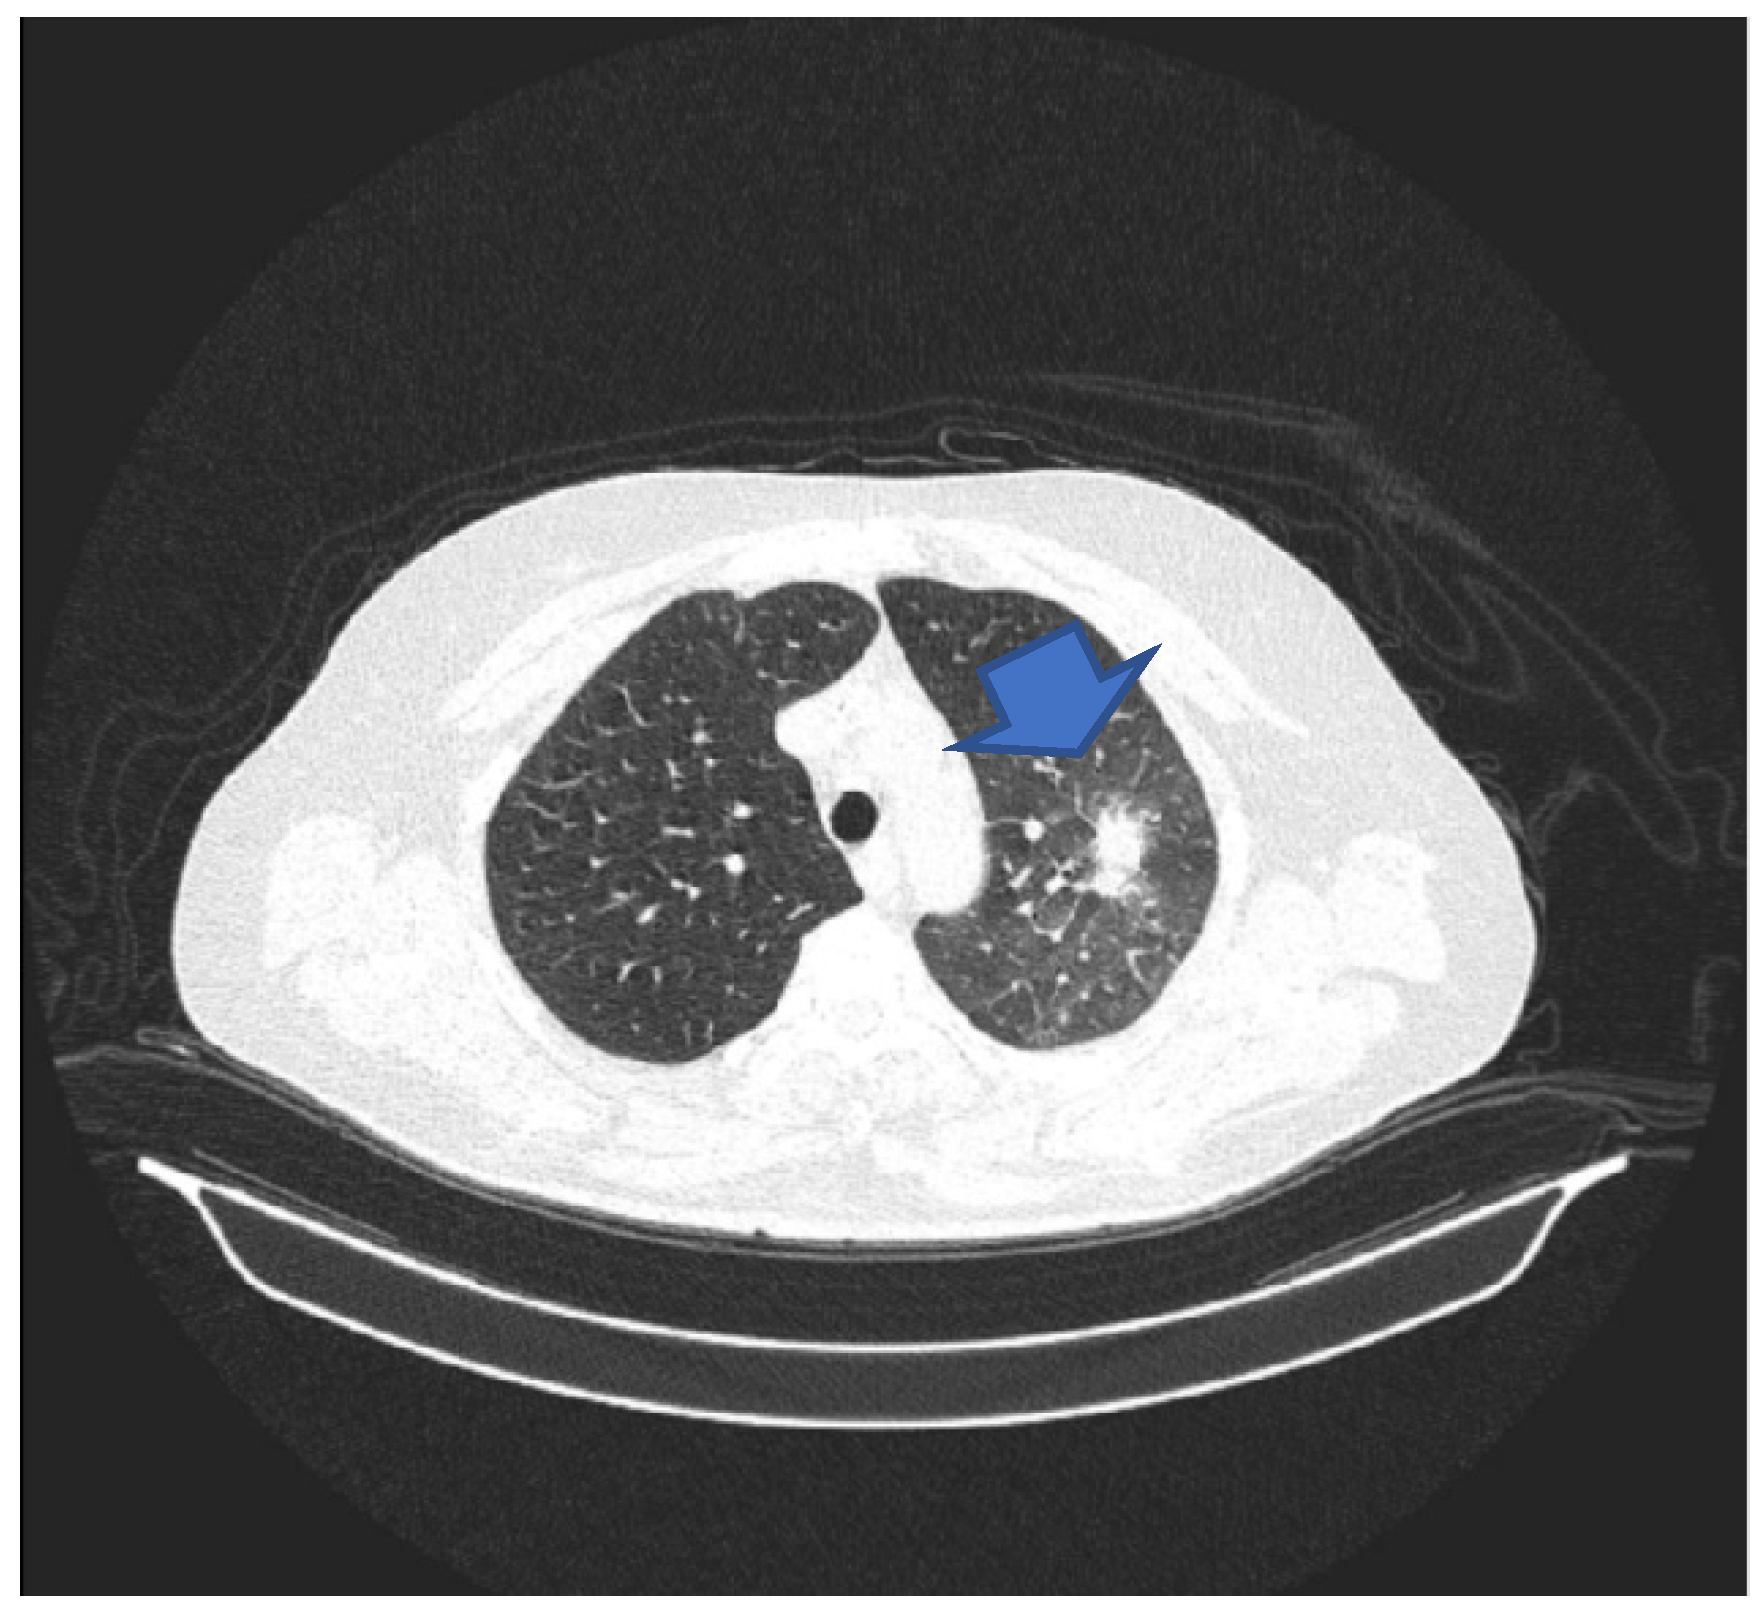

A control bone marrow puncture at the next admission was performed, and the results showed rich cellularity with 3% blast cells. The patient was again admitted in order to undergo consolidation chemotherapy. Soon after hospitalization, a CT scan was performed, which illustrated the radiological resolution of the two consolidations in the upper lobes but with the persistence of a lesion consistent with the radiological diagnosis of aspergilloma (Figure 1).

Figure 1. CT scan suggestive of pulmonary invasive aspergillosis. The arrow shows the location of the lesion.